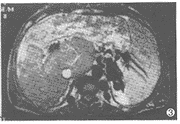

19例中,肝脏增大18例(95%),尾叶增大14例(74%)。14例(74%)肝脏信号不均,T2WI呈斑片状稍高信号,T1WI呈稍低信号且较明显(图1~3)。7例(37%)显示下腔静脉入右心房处阻塞;4例(21%)下腔静脉内有血栓影,表现为T1WI呈等信号,T2WI呈稍高信号;下腔静脉肝后段裂隙样狭窄10例(53%)。19例(100%)均显示肝静脉狭窄或阻塞,其中累及左肝静脉15例,中肝静脉13例,右肝静脉11例。17例(89%)见有肝内侧支血管呈“逗号”样或迂曲、走行无规律的血管影,5例(26%)显示有副肝静脉,呈粗大的血管影自肝右叶连于下腔静脉的右侧壁(图4~6)。17例(89%)见有肝外侧支血管,其中7例腹壁静脉曲张,14例(74%)有粗大的奇静脉和/或半奇静脉影,膈下静脉曲张3例,胃底静脉曲张3例。脾脏增大16例(84%),7例(37%)有腹水。

图2 与图1同一病例。静脉造影显示肝静脉部分阻塞,肝内侧支血管

超声、CT、静脉造影是BCS的常用检查方法,其中静脉造影是诊断以及介入治疗本病的主要依据。静脉造影可以明确狭窄或阻塞的部位和类型,了解侧支血管。MRI检查有无创性、多平面、多参数等优点[1~4],对于显示肝脏大小、形态以及邻近的实质性脏器优于超声和静脉造影。BCS常表现为肝脏增大,本组有18例显示肝脏增大。尾叶由于有单独的静脉回流到下腔静脉,增大较明显,本组有14例。区域性肝脏充血、中央小叶坏死及含水量的增加使得肝脏信号不均匀[3],T1WI呈低信号,T2WI呈高信号。T1WI、T2WI均呈低信号则提示肝纤维化。本组中14例有肝信号不均的表现,T1WI显示例数较T2WI稍多。